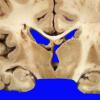

Subcortical Arteriosclerotic Encephalopathy (6)